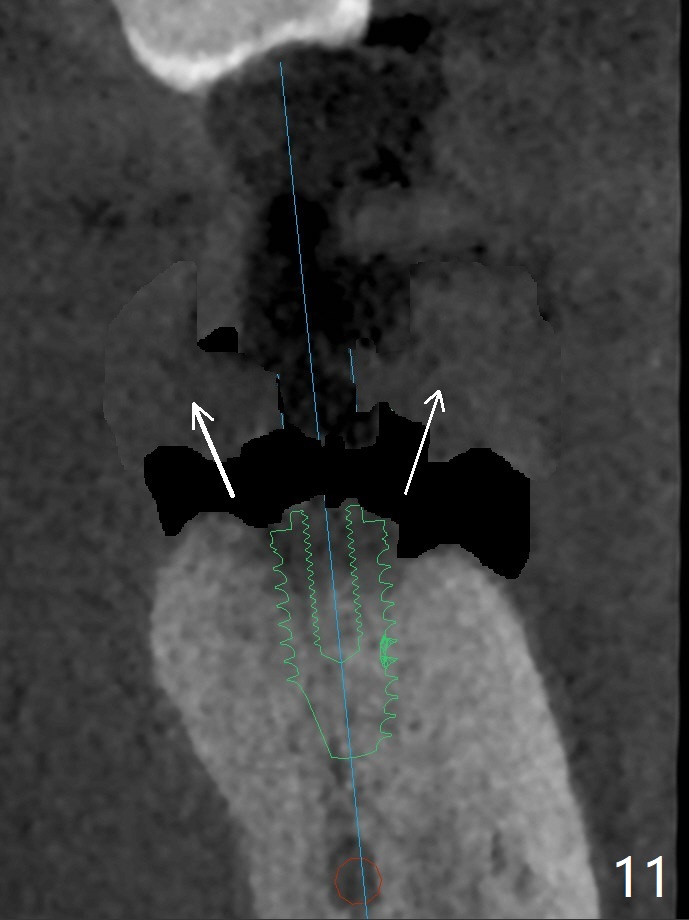

50岁男两年前不肯拔除左下7(图一),现在主动要求治疗(图二),需要做位点保留?怎么做的好?怎么收拾不动脑筋的惨剧(图三:仅远中牙槽窝植骨)?其实需要掀开近中粘骨膜(图四:箭头),然后植骨(红圆圈)。术后4.5个月近中缺损(图五:*),需要植牙植入很低(图六),离邻牙CEJ(<)很远。因此植体应该植入浅些(图七(CT矢状切面):箭头),离牙龈3毫米。放置袖3毫米(图八:粉红色)基台(紫色),然后在基台和植牙浅部植入粘性骨粉(图九:红圆圈)以及PRF膜(蓝线)。从冠状切面来看,颊侧(图十:B)需要多植骨,植牙前翻瓣(图十一:箭头),放置基台后(图十二),放置骨粉,膜,缝合。No Deviation 14 手术 Xin Wei, DDS, PhD, MS 1st edition 09/22/2020, last revision 03/02/2021